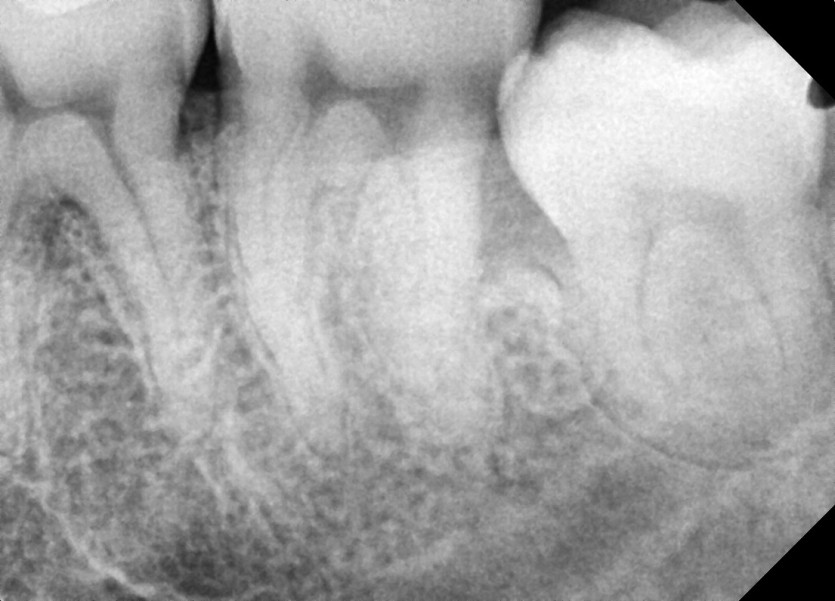

#38 사랑니 발치

구강 외과 전문의가 당일 발치했습니다.